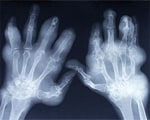

Gout, a common and painful inflammatory arthritis, is caused by elevated uric acid levels in the blood. To evaluate the risk factors for gout, researchers analysed data from American 2,476 women and 1,951 men who took part in the Framingham Heart Study. The participants were in their mid-40s and free of gout at the start of the study.

After a follow-up of 28 years, there were 104 gout cases in women and 200 in men. The gout incidence per 1,000 person-years was 1.5 in women and 4.0 in men. Women with serum uric acid levels over 5 mg/dL had a significantly lower risk of developing gout than men with uric acid levels over 5 mg/dL.

Risk factors independently associated with higher risk of gout in women were: increasing age, obesity, alcohol consumption, diuretic use and hypertension.

Women with serum uric acid levels greater than 8 mg/dL had a 46-fold higher risk of gout compared to those with levels less than 5 mg/dL. However, the magnitude of the association between uric acid levels and gout among women was significantly lower than for men.